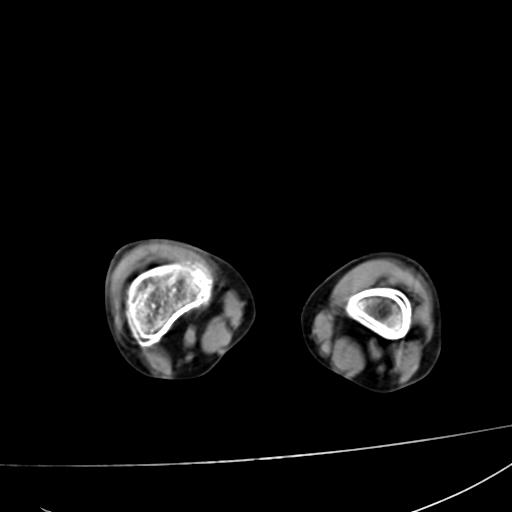

标题: PED0940:M12Y,左股骨下端酸痛畸形 [打印本页]

标题: PED0940:M12Y,左股骨下端酸痛畸形

12岁男孩,左膝关节肿痛8年,近月明显

内生骨软骨瘤?

血友性关节病?